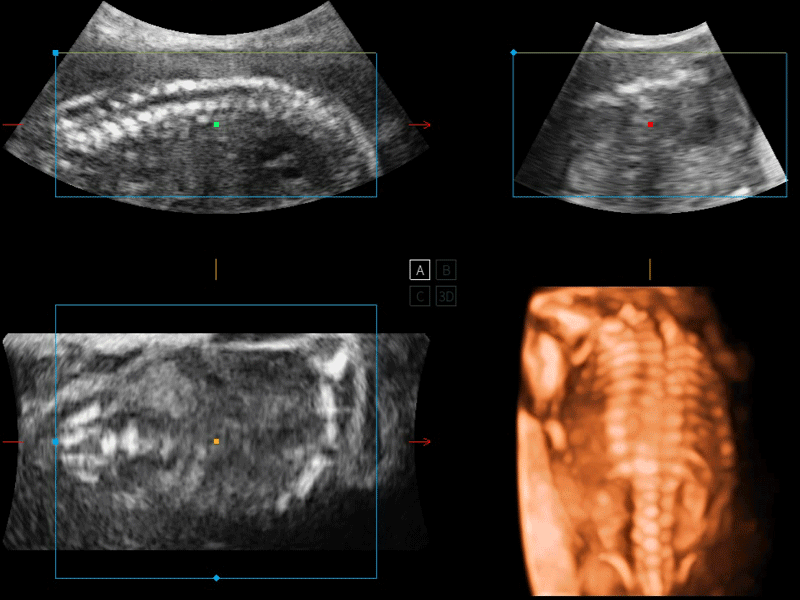

開立醫(yī)療通過不斷的技術(shù)創(chuàng)新,為大眾的生命健康提供持續(xù)關(guān)愛。P12 Plus采用全新一代超聲成像平臺(tái),新平臺(tái)旨在將真實(shí)還原組織解剖結(jié)構(gòu)作為首要目標(biāo)。平臺(tái)采用全新集成化硬件模塊,搭載新一代芯片,系統(tǒng)性能得到大幅提升,為您的診斷提供了豐富的臨床信息。優(yōu)異的圖像表現(xiàn),豐富的探頭配置,全面的應(yīng)用功能,為您日常診斷提供了可靠的助手。

P12 Plus

彩色多普勒超聲診斷系統(tǒng)